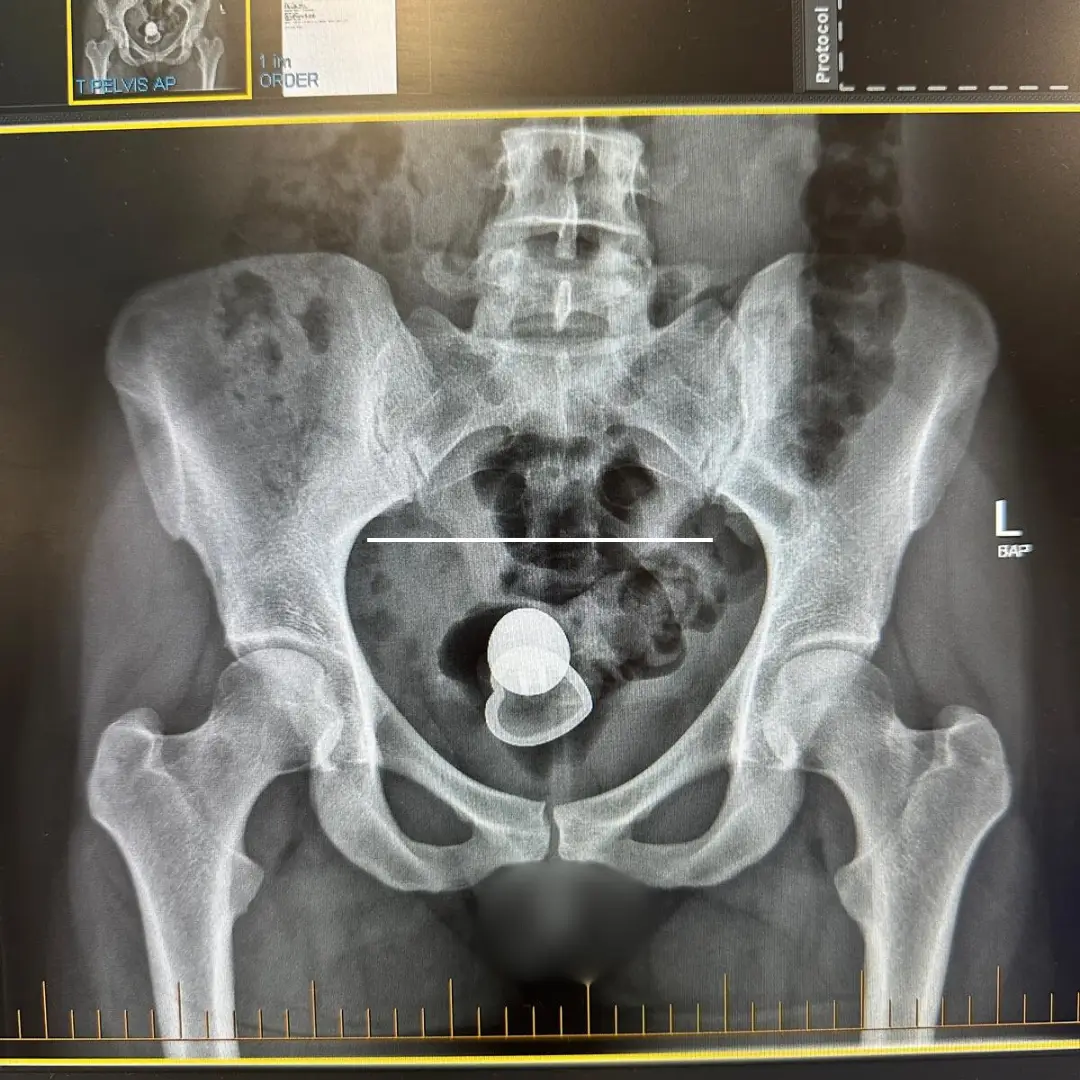

“I was on a first date with a guy, we started to have sex and decided to use an anal plug during sex, when all of a sudden it felt like the anal plug came out of me," Alicia said.

"So we stopped, and I put my hand down there to discover that it was gone. I couldn't feel the flared-out base of the plug. "We started pulling the doona [Aussie term for duvet] off the bed, pulling the pillows off the bed, looking underneath the bed for it... and i'm like, where the f*** is it?!”

Yep, it had disappeared inside of her. Alicia said: "I remember saying 'are you f***ing kidding me?'."

After trying to sort the issue at home, the best efforts of her and her date fell short. Hospital was the only option left. "Gravity was definitely doing its thing," she openly said.

Alicia was left waiting for surgery after more failed attempts to remove the object from her body. She said: "The nurses told me I would need to be put to sleep for surgery, so my body would be relaxed enough for them to

remove it.

"They were hoping to slot me in somewhere and said it should only take five minutes to complete. However the hospital ended up being so busy that I wasn’t able to have the surgery for another two days. So I waited in a hospital bed for two whole days with an anal plug lost inside of me.”